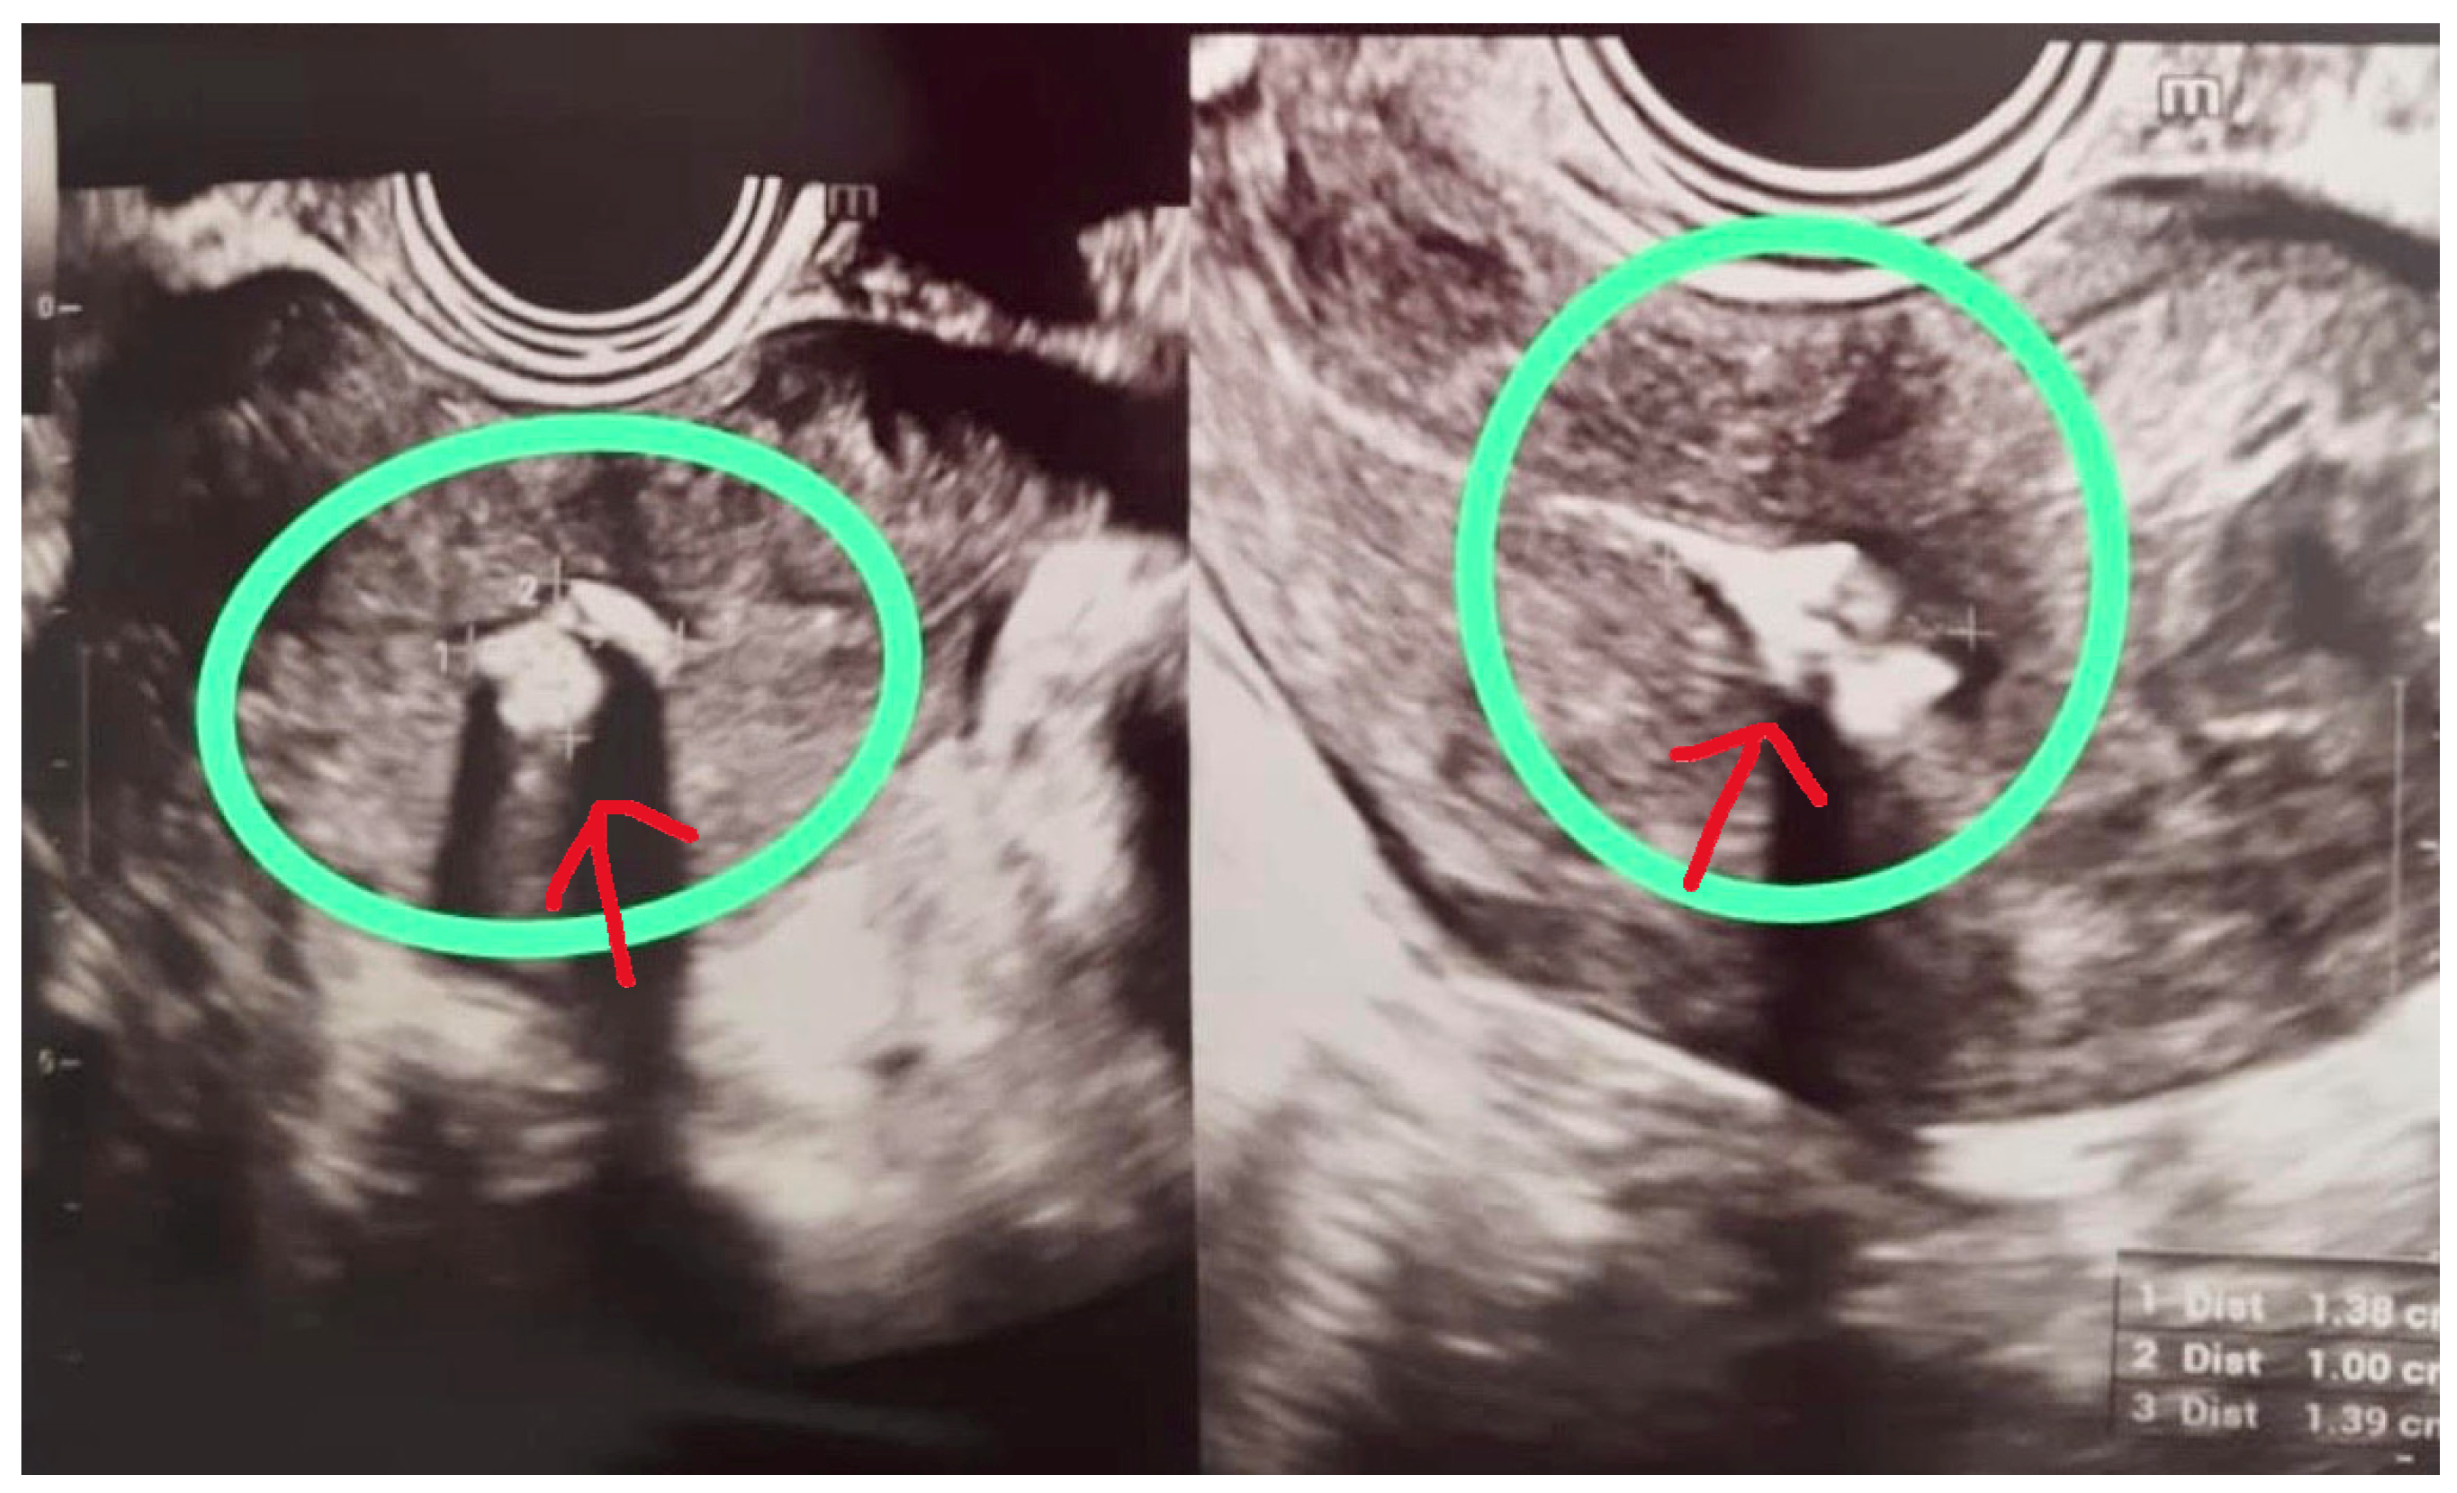

During a routine follow-up visit four months after delivery, her referring gynecologist performed a transvaginal ultrasound that revealed a hyperechoic endometrial lesion measuring 13 × 10 × 14 mm, located in the right lateral portion of the uterine cavity. Color Doppler evaluation demonstrated minimal vascularity (color score 1, minimal Doppler vascularity), consistent with retained amniochorionic tissue rather than vascularized RPOC (Figure 1). These features—small size, minimal vascularity, and late postpartum presentation—were considered favorable for an office hysteroscopic approach.

Figure 1. Transvaginal ultrasound image showing a hyperechoic, avascular lesion (circled) in the right lateral uterine wall.